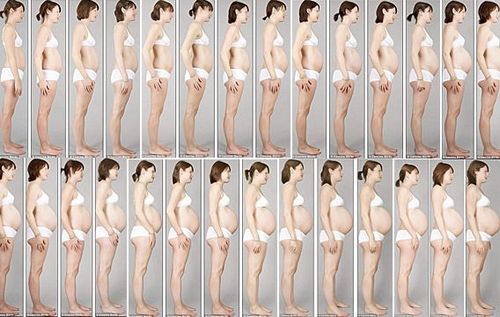

Вагітність довжиною 42 тижні і пологи за 10 годин

Вітаю! Нарешті є, у кого запитати! У мене 2 доньки (6 років і 1). Обидві народилися в 42 тижні від останніх місячних.

Перший раз: в 42 тижнів. несподівано відійшли води, сутичок немає, в пологовий будинок приїхали ввечері, почалися легкі перейми, вночі мені дали знеболюючу пігулку і веліли спати, вранці дали іншу таблетку - пішли сутички через 1 хв. матка не відкривалася, зробили епідуральну анастезію - через годину відкрилася, коли пройшла анастезія, я народила - порвалася жахливо - більше місяця ледве ходила. Дитина здорова, переношеності немає.

Другий раз: вагітність проходила чудово, 42 тижнів. - Відчуваю себе відмінно, дитина (судячи по УЗД) в повному порядку, але вилазити не збирається, за направленням лікаря їжу в пологовий будинок, сутичок немає, мені ставлять водорості - матка відкрити не 2 см, сутичок немає, мені вводять цей жахливий блакитний гель - дикі сутички щохвилини протягом 8 годин, матка не відкривається, мені роблять епідуралку - через годину матка відкрилася, сутичок немає, мені ставлять крапельницю, після якої нарешті починаються сильні потуги, і через 10 хв народжується моя дочка, а мене знову зашивають. Дитина здорова, переношеності немає.

Не секрет, що для кожного плоду потрібно свого часу на дозрівання. Судячи з усього, у вас були пролонговані вагітності, тобто більш тривалі. Переношування характеризується рядом ознак, які визначають за даними УЗД (стан плода і плаценти, плацентарний і пуповину кровотік, кількість і якість навколоплідних вод, кістки черепа з швами і джерельця плода і т.д.), гормонального фону вагітної, результатами амніоскопіі (візуально оцінюють навколоплідні води за допомогою спец. мікроскопа). Основний метод це УЗД. Я не знаю де ви народжували, які у них поняття і правила. Розповім, як рекомендують знаючі люди. (Французькою акушер гінеколог Мішель Оден) Тактика така: після 40недель спостерігають за станом плоду і чекають самостійних пологів. Основний, але не єдиний, метод спостереження -УЗД з допплером. В залежності від ситуації, щодня. Якщо стан плода погіршується або ще якісь фактори приєднуються, то роблять Кесарів розтин. Але це при подтверденіі пренашіванія! У преношенного плода більш щільні і малорухливі кістки черепа, а це чревате наслідками. До того ж при переношуванні порушуються функції плаценти, плід може страждати від гіпоксії. А стимуляція, провокування свідомо ризикованих пологів, заводить у глухий кут. Переношування - це збій в системі мати-плпцента-плід, дуже непроста система! Якщо це пролонгована вагітність, чекають початку родової діяльності і далі як природою передбачено Головне враховувати потреби жінки в пологах!